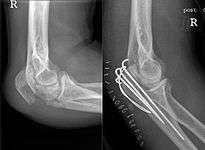

Frontal and lateral X-ray views of the elbow are typically done to investigate the possibility of an olecranon fracture. A standard lateral view of the elbow insufficient to diagnose olecranon fractures. A true lateral x-ray is essential to determine the fracture pattern, degree of displacement, comminution, and the degree of articular involvement.

In fractures with little or no displacement, immobilization for 4 to 6 weeks may be sufficient, but other cases need surgery, using pins, wires for tension band wiring, screws only, or plates and screws.